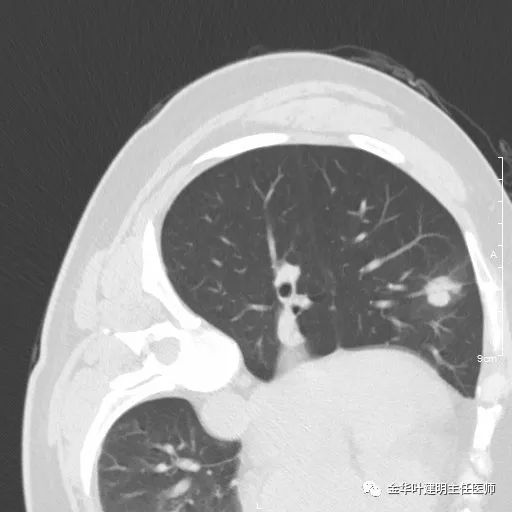

七、浸润性腺癌的其他型:

上图此例实性结节,是实体型,我们发现其影像特征: 病灶有浅分叶、细毛刺、支气管截断征、膨胀性,密度高而密 (比腺泡型实、比粘液癌高、比鳞癌或小细胞癌更具膨胀性)。

但是上面这几例,因为不管怎样的组合,都是实性密度+实性密度,这时仅从影像上就非常难以判断具体的亚型,不过,我们要根据相关的影像特征判断它为恶性,而且该尽早取得病理依据,能手术的要抓紧、不能手术的也要穿刺等得到病理类型的确诊后积极治疗,这就够了!